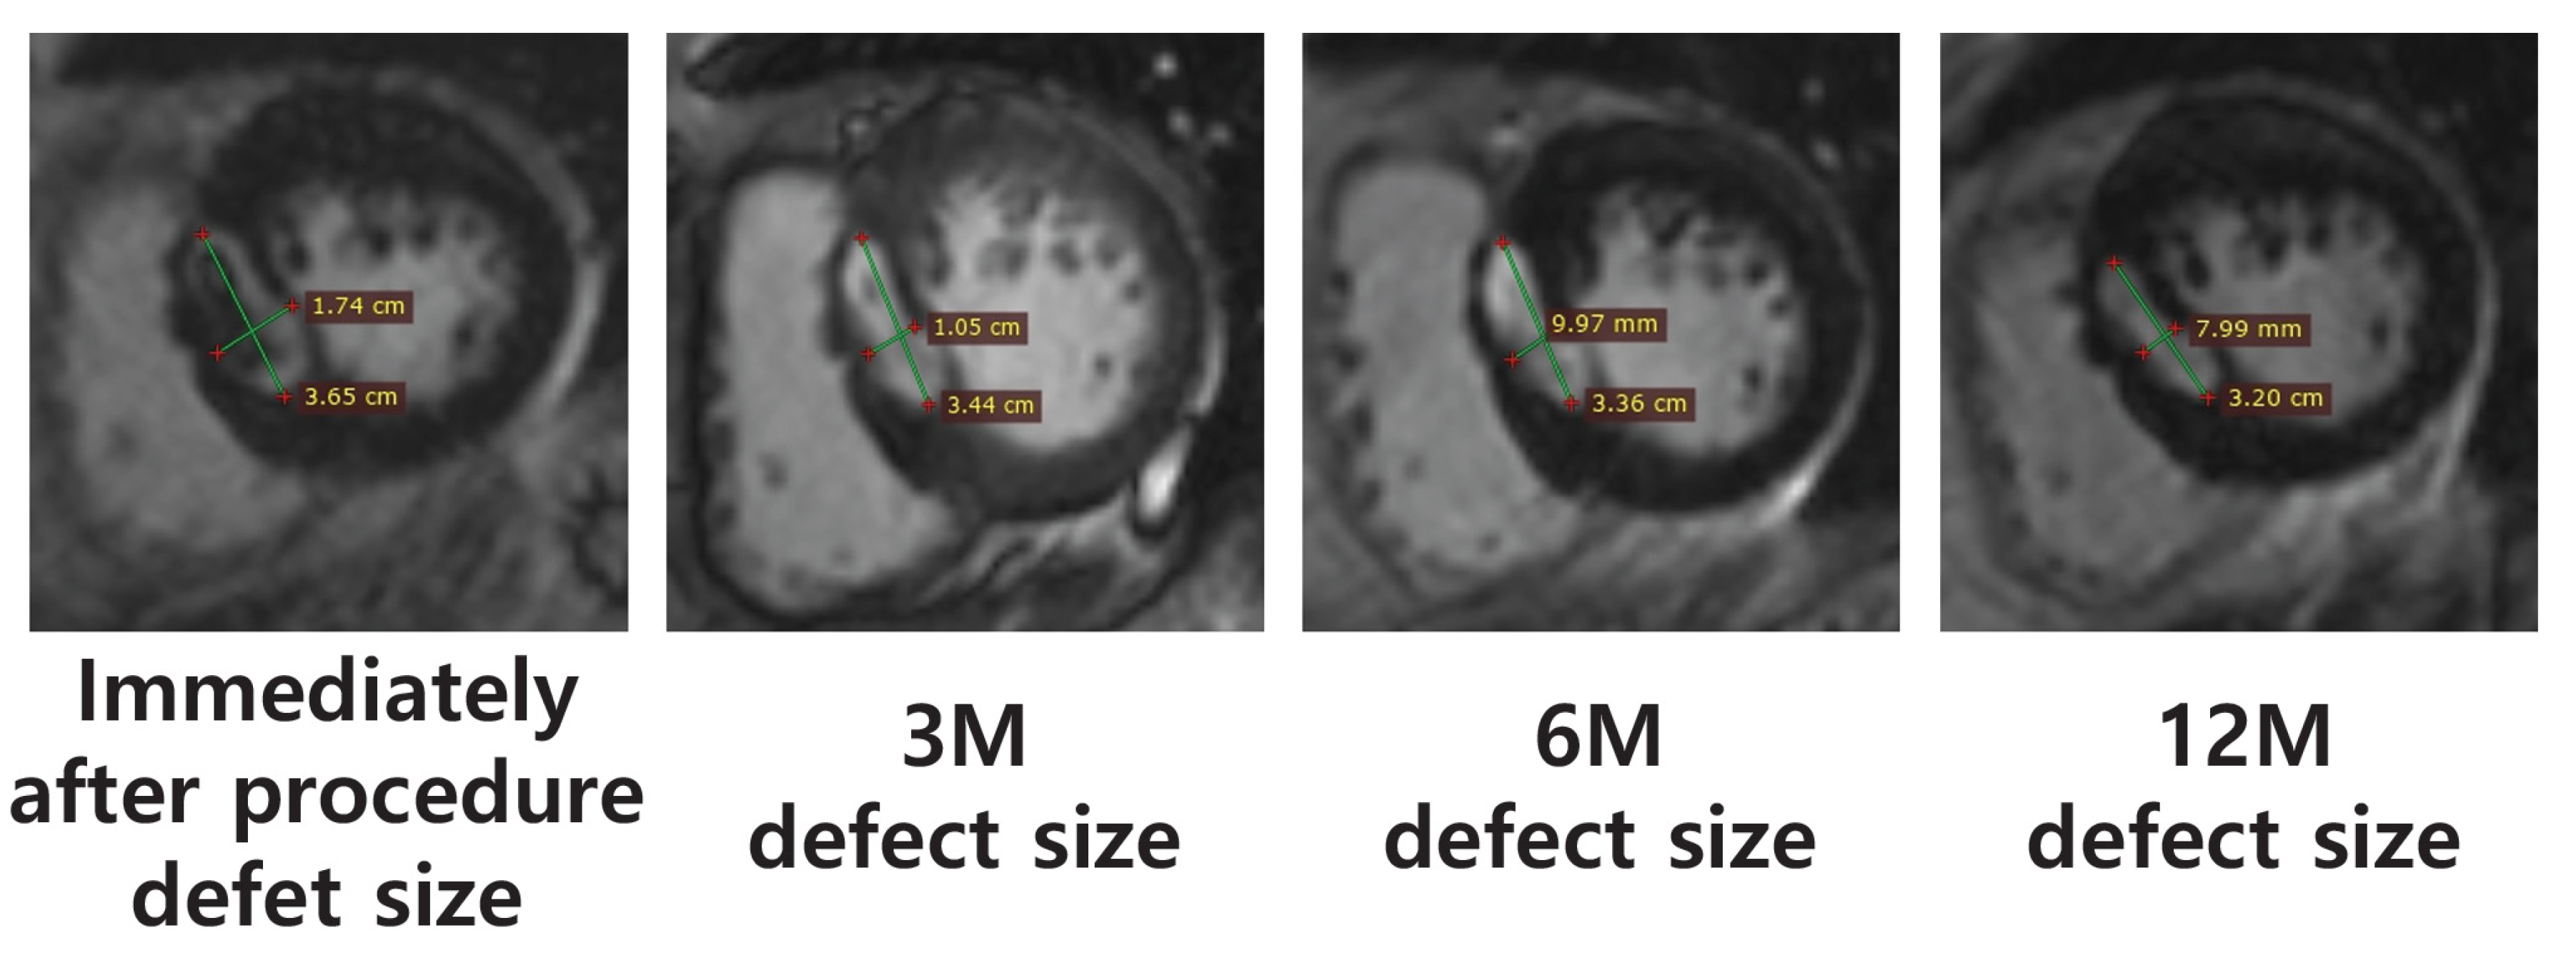

| Case | Ablation Defect Size (MRI, mm) | |||

|---|---|---|---|---|

| Immediately Following Procedure | 3 M | 6 M | 12 M | |

| 1 | - | - | - | - |

| 2 | 36.5 × 17.4 | 34.4 × 10.5 | 33.6 × 10.0 | 32.0 × 8.0 |

| 3 | 25.7 × 18.9 | 16.6 × 11.4 | 14.4 × 7.8 | 13.0 × 7.7 |

| 4 | 12.6 × 12.3 | 11.3 × 10.5 | 9.6 × 10.1 | 9.7 × 8.7 |